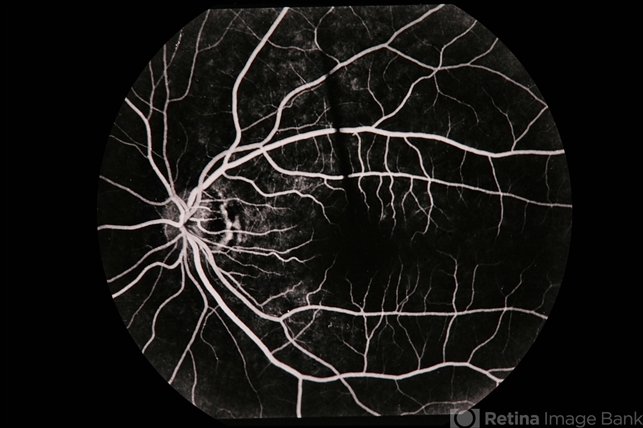

presumed ocular histoplasmosis syndrome (POHS), Lyme disease

Pseudo-POHS / lyme.